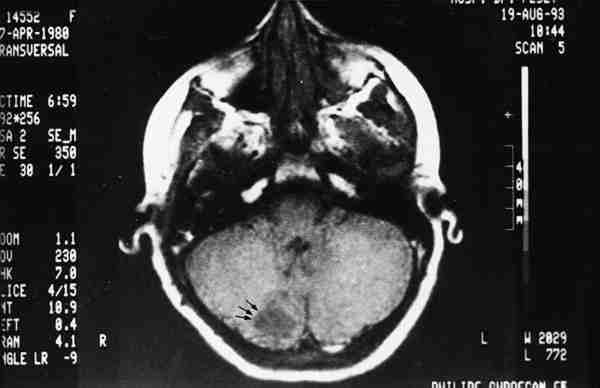

Figura 12

TAC SIN CONTRASTE: IMAGEN HIPODENSA A NIVEL DE HEMISFERIO CEREBELOSO DERECHO.